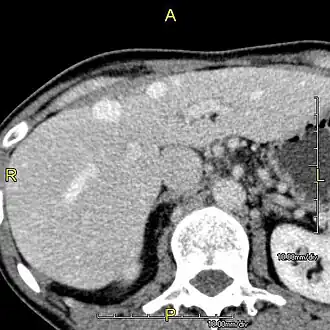

With the recent advances of noninvasive imaging, living liver donors usually have to undergo imaging examinations for liver anatomy to decide if the anatomy is feasible for donation. The evaluation is usually performed by multidetector row computed tomography (MDCT) and magnetic resonance imaging (MRI). MDCT is good in vascular anatomy and volumetry. MRI is used for biliary tree anatomy. Donors with very unusual vascular anatomy, which makes them unsuitable for donation, could be screened out to avoid unnecessary operations.

-

MDCT image. Arterial anatomy contraindicated for liver donation -

MDCT image. Portal venous anatomy contraindicated for liver donation -

MDCT image. 3D image created by MDCT can clearly visualize the liver, measure the liver volume, and plan the dissection plane to facilitate the liver transplantation procedure. -

Phase contrast CT image. Contrast is perfusing the right liver but not the left due to a left portal vein thrombus.